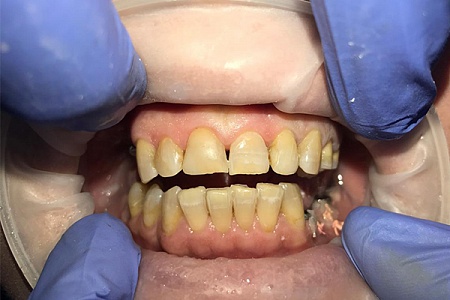

Работы наших врачей